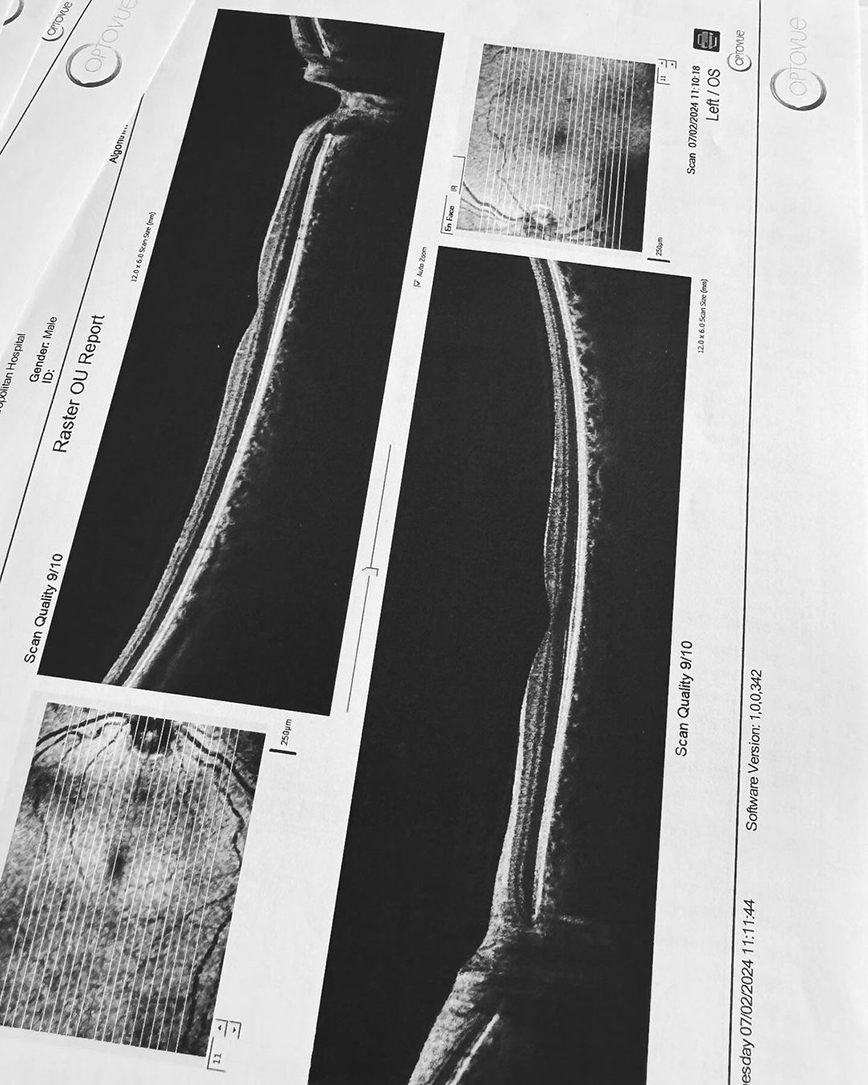

Ακούω κατά καιρούς διάφορες φήμες και έτυχε να ακούσω και τώρα κάποιες άλλες που δεν τιμούν οποίους τις διαδίδουν, οπότε θα ανεβάσω μερικές φωτογραφίες από τις δύο δύσκολες τελευταίες εβδομάδες. Ο πιο σημαντικός λόγος που τις ανεβάζω είναι όμως για να μοιραστώ την ιστορία μου για την αμφοτερόπλευρη δακρυοαδενίτιδα.

Αιτία ο κοβιντ ο άτιμος…Ψάξτε το. Μπορεί και κάποιος από εσάς να υποφέρει από αυτήν αυτό τον καιρό και να μην ξέρει πως να το διαχειριστεί.. Εγώ μπήκα στο νοσοκομείο και είχα την πιο απίστευτη γιατρό την Δήμητρα Π. να με προσέχει σε κάθε βήμα. Είμαι καλά τώρα όποτε πάμε γερά!», έγραψε στην ανάρτησή του ο Χρήστος Μάστορας.